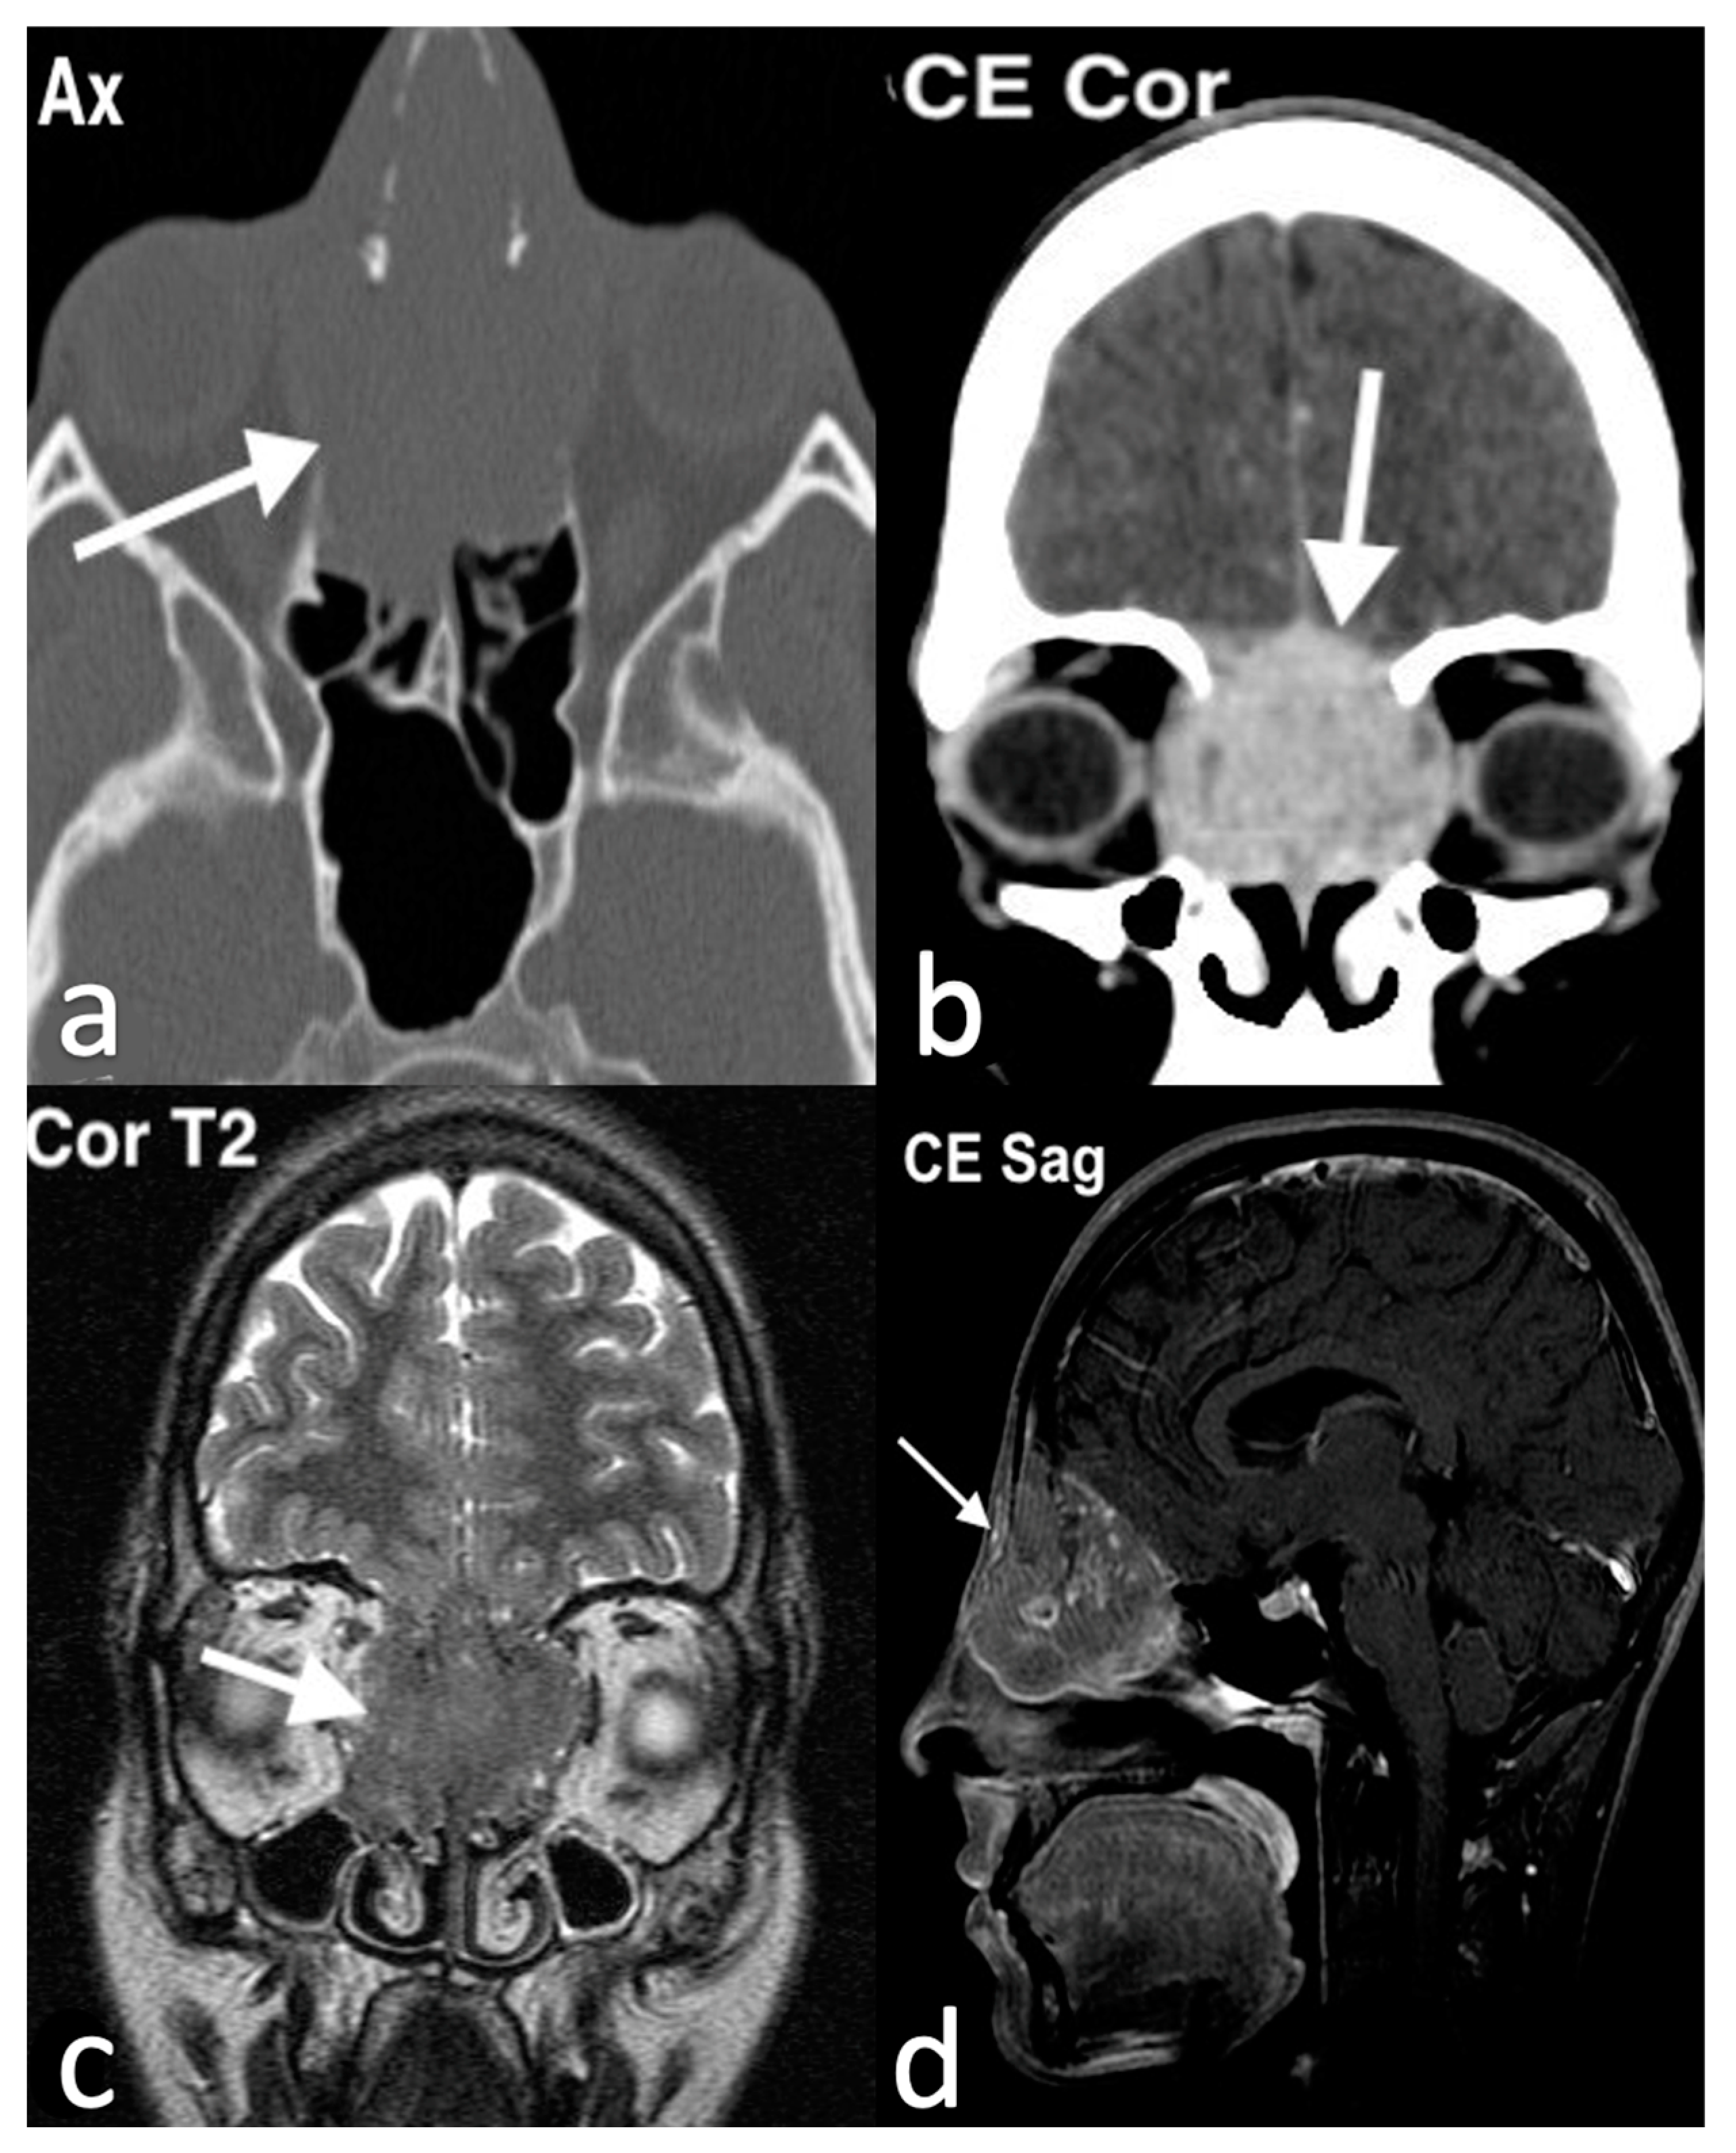

3.3.2. Esthesioneuroblastoma

3.3.3. Intestinal-Type Adenocarcinomas